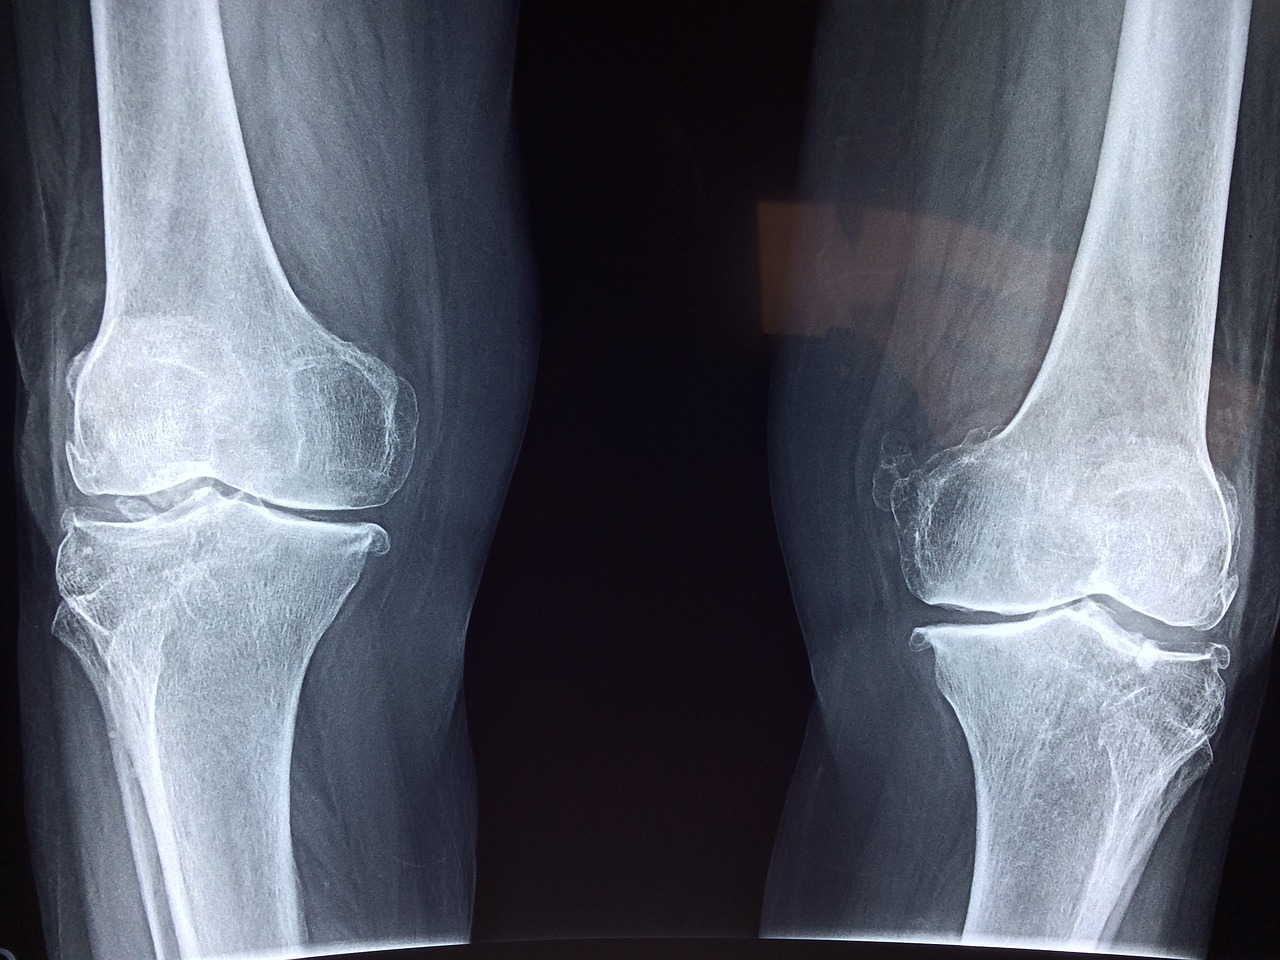

4. 진단 방법

- 가성통풍: 관절액 검사로 결정의 유무를 확인.

- 일반 통증: X-ray, MRI 등으로 구조적 이상 검사.